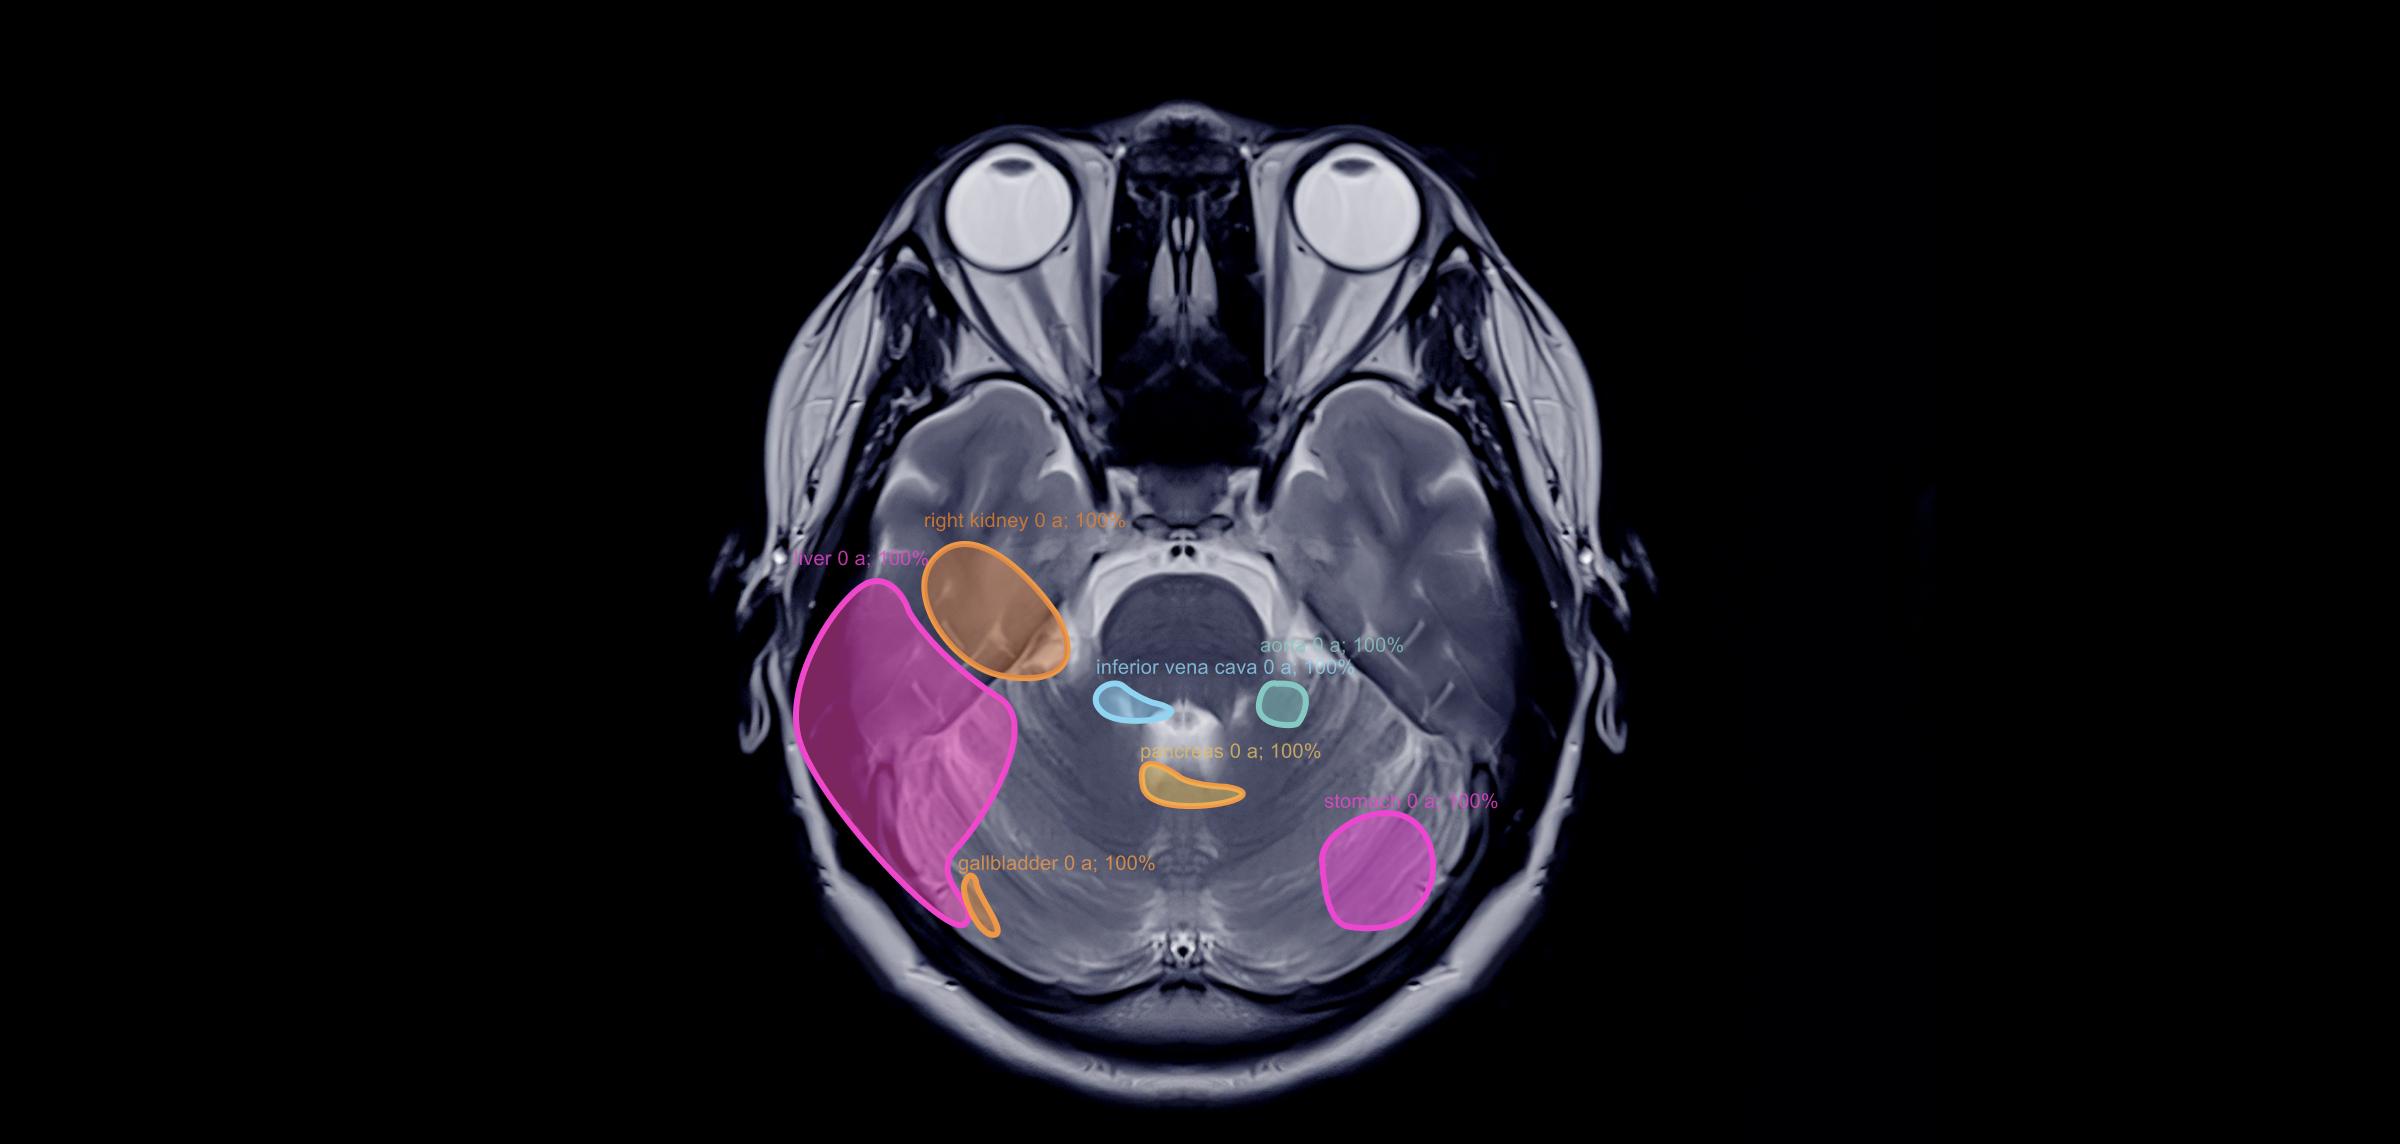

AI segmentation medical imaging is a computer vision technique that identifies specific parts of a medical image based on various criteria. Its main goal is to isolate areas of interest within the image, which is crucial for object recognition, scene understanding, and medical image analysis.

When a detailed understanding of different objects or regions in an image is needed, semantic segmentation comes into play. This technique classifies each pixel in an image into a specific class or category, providing a precise analysis of the image's components.

AI-based algorithms help identify specific structures within medical images and provide precise quantitative analysis of areas of interest.

Unlike semantic segmentation, instance segmentation assigns a unique tag to each distinct object in the image, rather than grouping all pixels of a particular class. This approach is essential when multiple objects of the same class appear in close proximity, allowing for precise differentiation between them.

Image segmentation is widely used to analyze X-rays, CT scans, MRI scans, and ultrasound images. For instance, in a chest CT scan, segmentation helps identify and outline the lungs, heart, and other vital structures, aiding in detecting abnormalities like tumors or lesions.

It can also differentiate between structures within a single organ and is especially valuable for analyzing smaller objects such as tissue samples or cells.